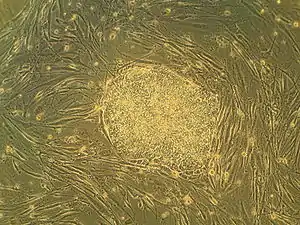

Embryonic stem cells (ESCs), derived from the blastocyst stage of early mammalian embryos, are distinguished by their ability to differentiate into any embryonic cell type and by their ability to self-renew. It is these traits that makes them valuable in the scientific and medical fields. ESCs have a normal karyotype, maintain high telomerase activity, and exhibit remarkable long-term proliferative potential.[7]

Embryonic stem cells of the inner cell mass are pluripotent, meaning they are able to differentiate to generate primitive ectoderm, which ultimately differentiates during gastrulation into all derivatives of the three primary germ layers: ectoderm, endoderm, and mesoderm. These germ layers generate each of the more than 220 cell types in the adult human body. When provided with the appropriate signals, ESCs initially form precursor cells that in subsequently differentiate into the desired cell types. Pluripotency distinguishes embryonic stem cells from adult stem cells, which are multipotent and can only produce a limited number of cell types.

Under defined conditions, embryonic stem cells are capable of self-renewing indefinitely in an undifferentiated state. Self-renewal conditions must prevent the cells from clumping and maintain an environment that supports an unspecialized state.[8] Typically this is done in the lab with media containing serum and leukemia inhibitory factor or serum-free media supplements with two inhibitory drugs ("2i"), the MEK inhibitor PD03259010 and GSK-3 inhibitor CHIR99021.[9]